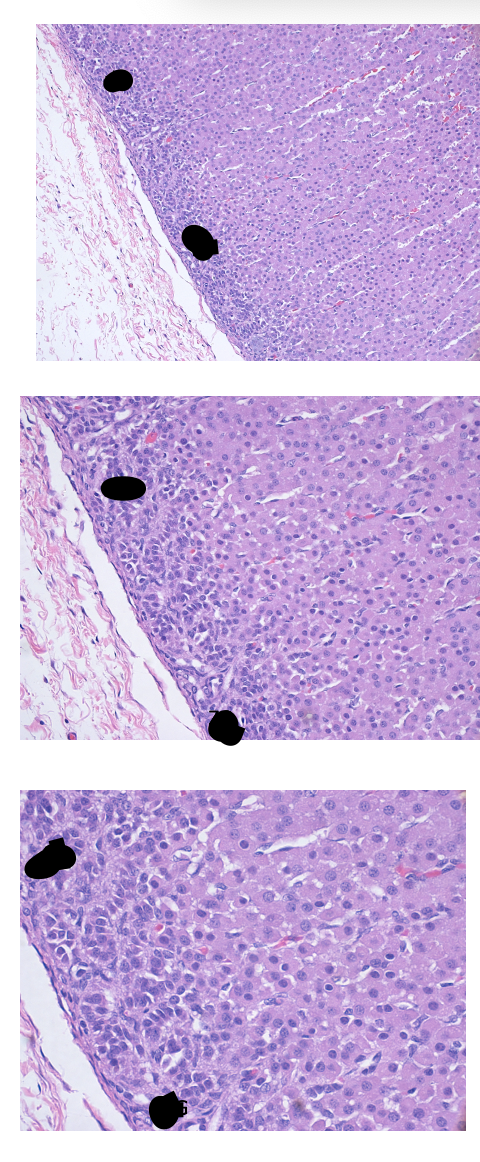

3

Q

A

Pars distalis

4

Chromophobes –> black arrows

Acidophils –> brown arrows

Basophils –> red arrows

5

Pars intermedia

6